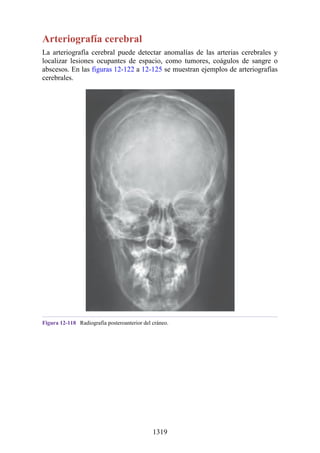

reparación plástica de los dedos se realiza a los 5 años de edad. La “mano en pinza de langosta” es

una forma de sindactilia que se asocia con una hendidura central que divide la mano en dos partes.